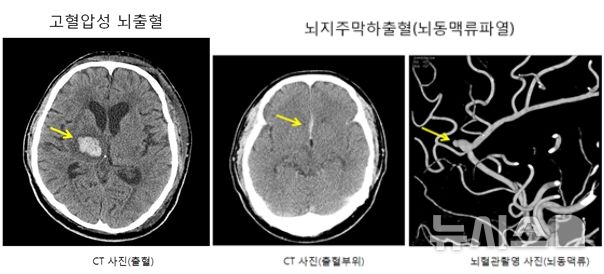

[서울=뉴시스] 왼쪽부터 고혈압성 뇌출혈과 뇌지주막하출혈(뇌동맥류파열). (사진= 국민건강보험 일산병원 제공)